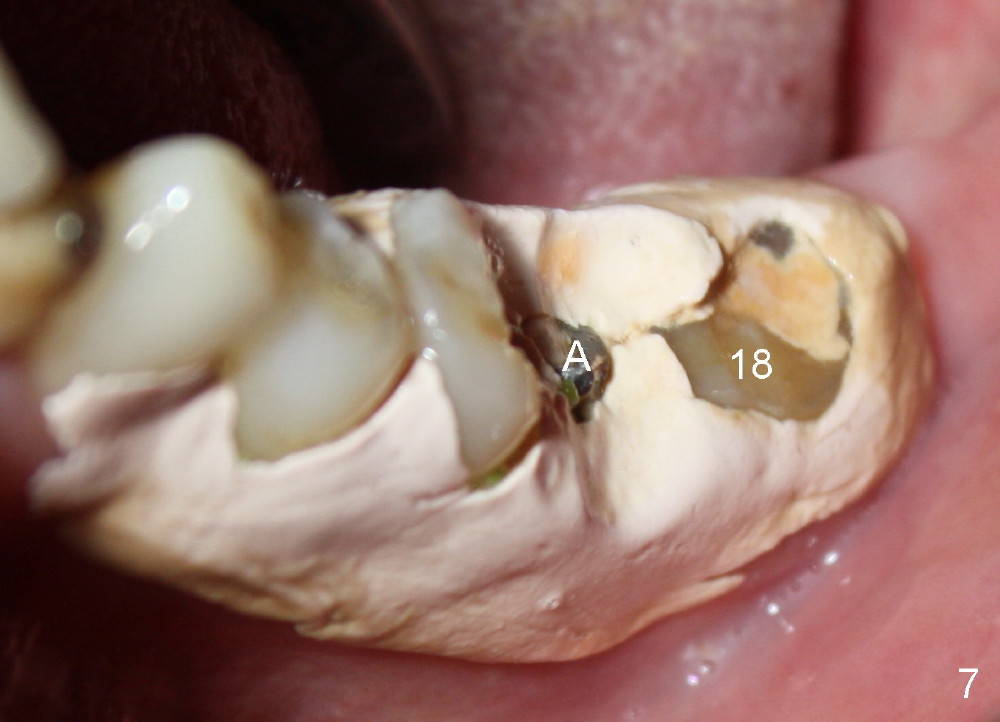

One week postop, the perio dressing stays in place (Fig.7). Then the patient is out of town. When he returns 3 weeks postop, the provisional bridge is fabricated as mentioned above (Fig.8). The provisional breaks down soon and are repaired multiple times, since there are multiple missing teeth. The patient is not eager to have ideal occlusion and wants restoration quick. We may try ortho in the upper right area.